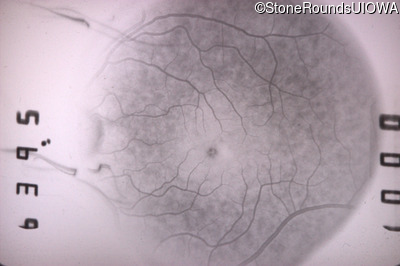

Fluorescein Angiography - Right - 20/25 +2 sc

Exemplar